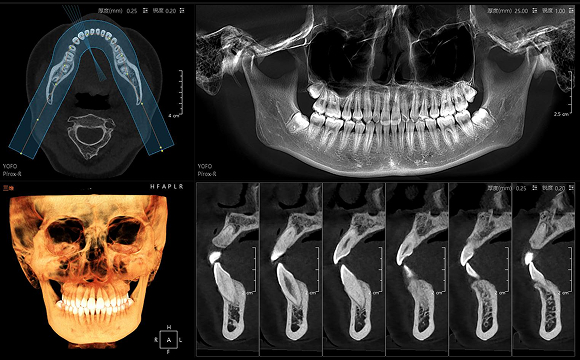

只需一次单圈扫描即可获得CT、3D全景和3D正/侧位影像,并能同时生成3D TMJ视图

提高诊疗效率,避免过度检查,减少患者所受的辐射

• CT

CT

• 3D全景

3D全景

• 3D 正侧位

3D 正侧位

16×15cm

非拼接大视野

28lp/cm

高精准